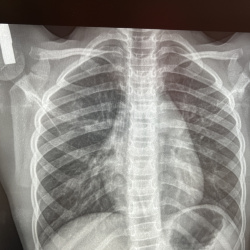

Возраст 7 лет. Жалоб нет. Что за тяжистая тень в прикорневой зоне правого лёгкого? В боковой проекции ее нет . Сначала думал может скиалогический эффект и повторил снимок, но эта же тень сохраняется...